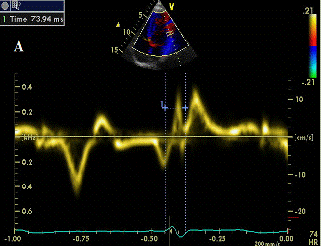

Рис. 1В Схема измерения интервал Q-Ts в сегментах правого желудочка

Межжелудочковый диссинхронизм оценивали по величине межжелудочковой механической задержки (МЖМЗ) рассчитанной в режиме импульсно-волнового допплера ЭхоКГ и импульсно-волнового режима тканевого допплера (МЖМЗТДМ). В режиме импульсно-волнового допплера ЭхоКГ синхронизированного с ЭКГ из парастернальной позиции на уровне корня аорты и из апикальной пятикамерной позиции измеряли время от начала QRS ЭКГ до начала потока в выносящем тракте правого (Q-ЛА) и левого (Q-АО) желудочков, разница между аортальным и легочным пресистолическим интервалом (QАО-QЛА) более 40 мс трактовалась как значимый межжелудочковый диссинхронизм [20]. В импульсно-волновом режиме ТДМ рассчитывали величину МЖМЗТДМ по разнице движения базальных сегментов правого и левого желудочков. Для этого измеряли время от начала зубца Q на ЭКГ до начала систолического движения соответствующего сегмента (рис. 1А, В), значение более 40 мс считали значимой МЖМЗ [21].